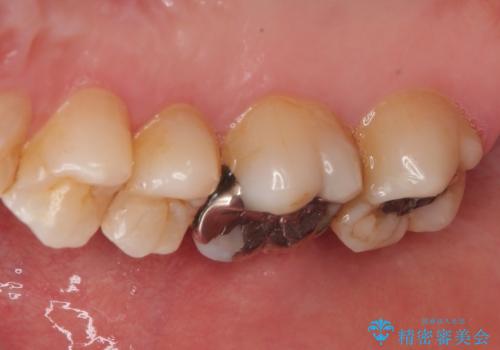

右上の6番目の歯はメタルインレーが大きかったためルジルコニアクラウン、右上の7番目の歯は一番奥で審美的な要素よりも機能面を重視してゴールドインレー修復による治療計画を立案しました。

拡大鏡視野下で保険のプラスチック(コンポジットレジン)、虫歯を除去し、フルジルコニアクラウン、ゴールドインレーに適した形にしました。

歯と歯茎の間に圧排糸と呼ばれる糸を入れてシリコーン印象を行いました。